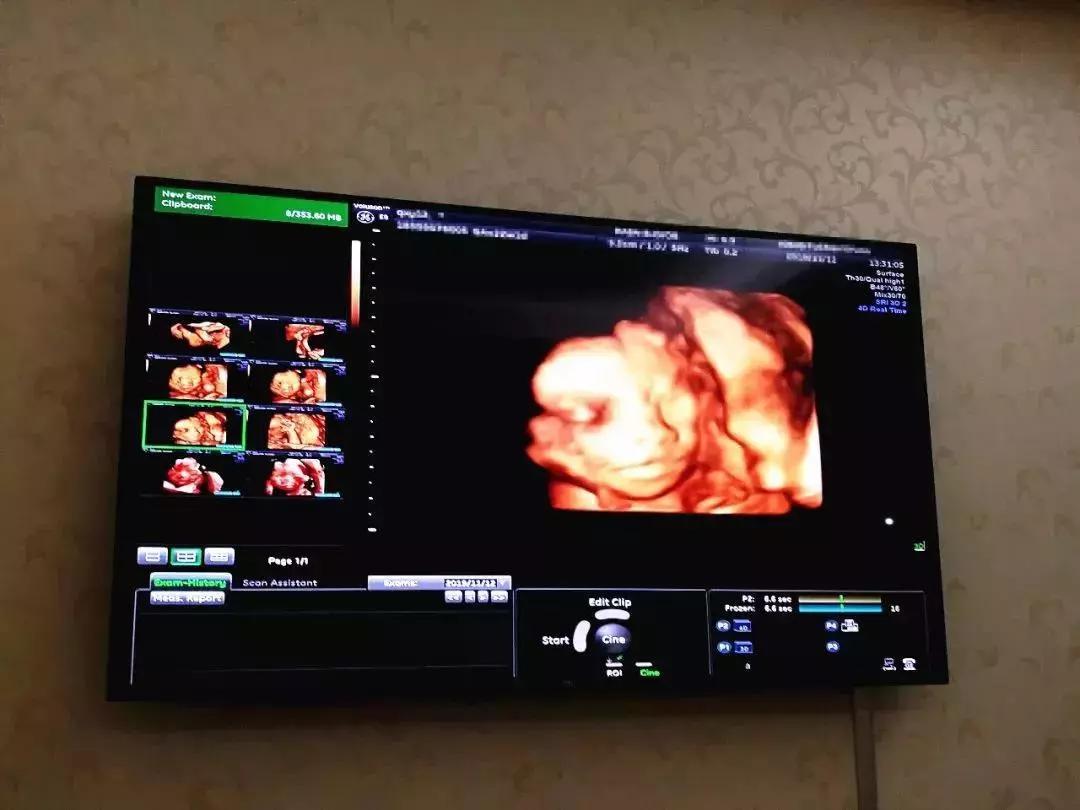

四维彩超火爆,门诊量2.5万+

四维彩超是孕妈妈圈的网红产检项目,不仅因为能较准确的诊断出胎儿严重畸形,还可与未出生的宝宝来一场穿越时空的相见。

由于技术力量、设备更新等原因,宁波地区所有医院并非都能够运用四维彩超技术。

而艾博尔妇产医院引进美国GE四维彩超设备,彩超医生又有多位专家坐镇,并允许家属进入检查室观看胎宝宝模样,而且采取预约制,合理错开了检查时间,准爸妈无需久等便可检查,因此很受准爸妈欢迎!

多年以来艾博尔四维彩超一直口碑极佳,经常出现一号难求现象,2019年的四维门诊量达2.5万+。因此建议孕妈妈一定要尽早预约,以免错过检查时间。PS,艾博尔预约无需费用,检查当天付款即可。